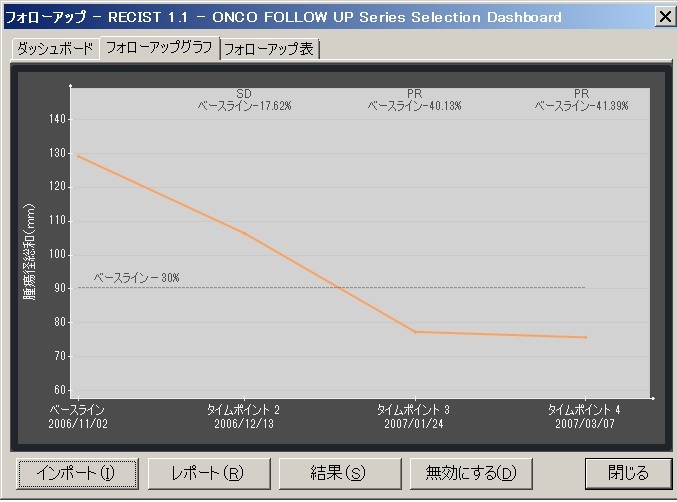

Myrian®XL-Onco 腫瘍の経時的フォローアップ・アプリケーション

効率的なフォローアップのための理想的なソフトウェア

フォローアップに必要なすべてのステップは自動化されています。 ベースライン作成後、次のタイムポイントでは自動的に非剛体レジストレーションが行われ、高速な検査比較が可能です。必要に応じて自動で国際評価基準(RECIST1.0,1.1)に沿った治療レスポンスが計算され、PACSへ転送されます。そし検査レポートも自動作成されます。

| 4.ダッシュボードでレスポンスグラフと一覧表を素早く確認 | |

|---|---|

|

|

|